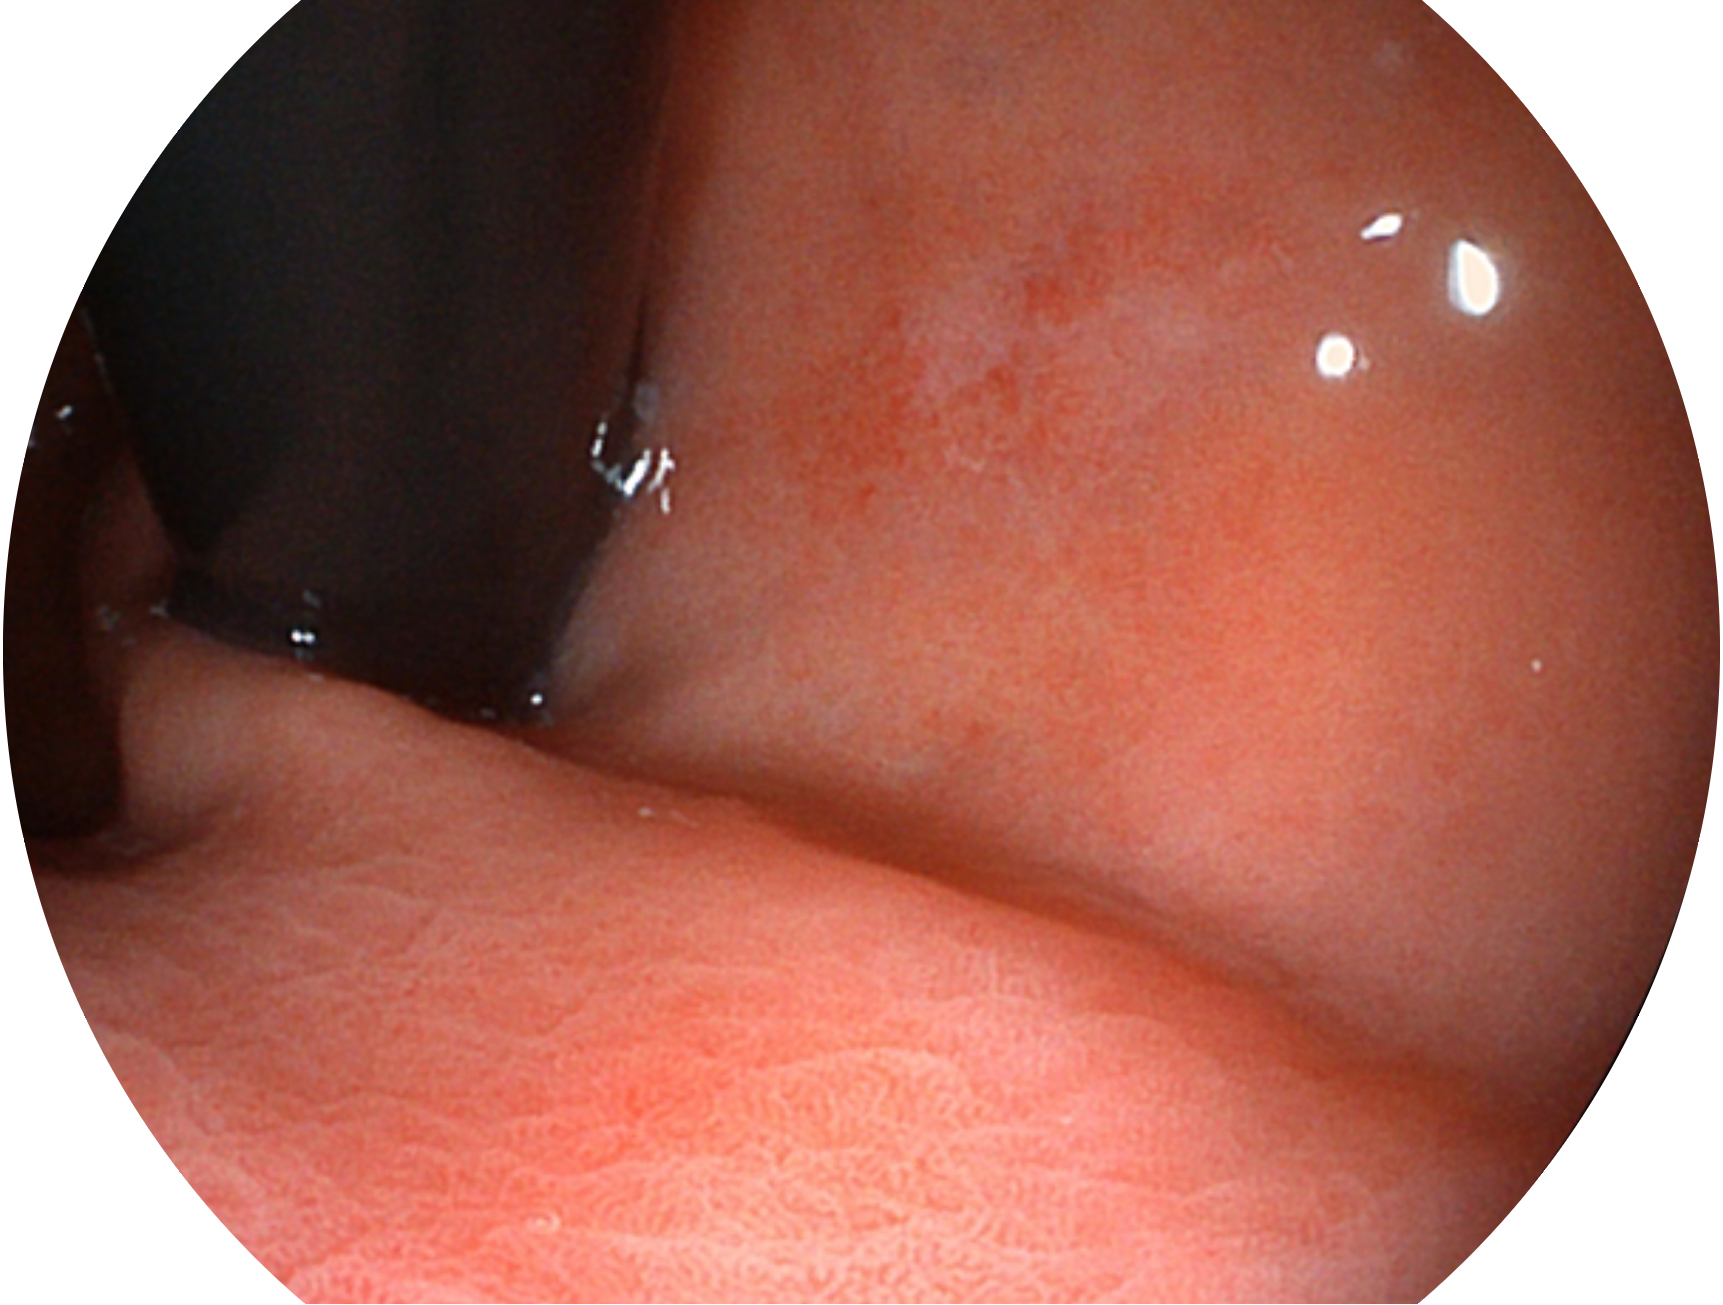

1xBET新开发的内镜染色技术,主要是基于多波长LED 光源的开发,VLS-55Q 四波长LED 光源是由四个不同颜色的LED光按照相应照明模式所规定的特定发光比例进行合束后形成,合束后形成的照明光的光谱由红光、绿光、蓝光及蓝紫光这四个不同的波段范围构成。具有更高光谱自由度,通过光谱比例的控制,实现了聚谱成像技术,英文全称为“Spectral Focused Imaging, SFI”,缩写为“SFI”和光电复合染色成像技术,英文全称为“Versatile Intelligent Staining Technology, VIST”,缩写为“VIST”。